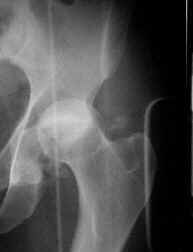

A) Post-operative Xr. B) Aspect of the frame. Total time with frame was 2 months. C) Xr control at 2 years of follow-up.

Clinical aspect at 2 years of follow-up.